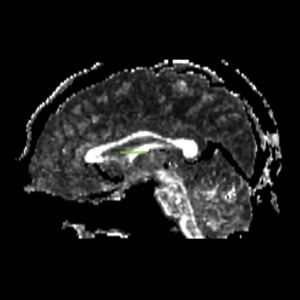

The ROI1 was drawn on the sagittal slice, 5 slices superior to the anterior commisure (Fig. 8 & 10). The ROI2 was drawn on a coronal slice where the crux of the fornix was present. It was not always the same slice for both sides (Fig. 9 & 11).

Figure 8. Axial View of ROI 1

Figure 10. Sagittal View of Fornix, ROI 1 (both left and right)

The color coding of the resulting ROIs is as follows:

ROI 1: Left & Right (16)

ROI 2: Left(5) - Right(15)